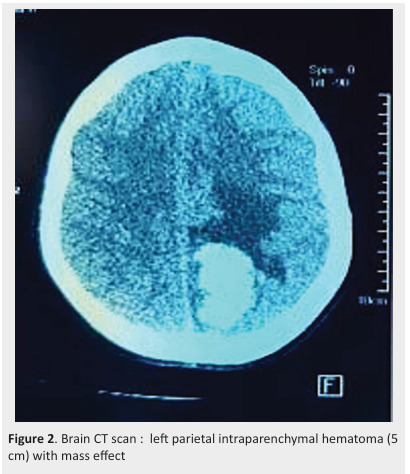

Methods: retrospective study collecting all cases of chronic ITP among children aged less than 14 years, in a department of pediatrics in south of Tunisia during a period of 13 years (from 1st January 2010 to 31 December 2022) Results: during the study period, 72 newly diagnosed ITP were recorded; 11 patients evolves chronic ITP (12 ,5%). They were 6 boys and 5 girls. Two patients were aged more than 10 years at the onset of the disease. Symptoms in the chronic stage were mucocutaneous bleeding. One patient developed post traumatic cerebral hemorragia. Three patients had severe form, and required second-line therapy. Two patients requested Eltrombopag with good response. One patient had spontaneous recovery after 3 years of follow up.